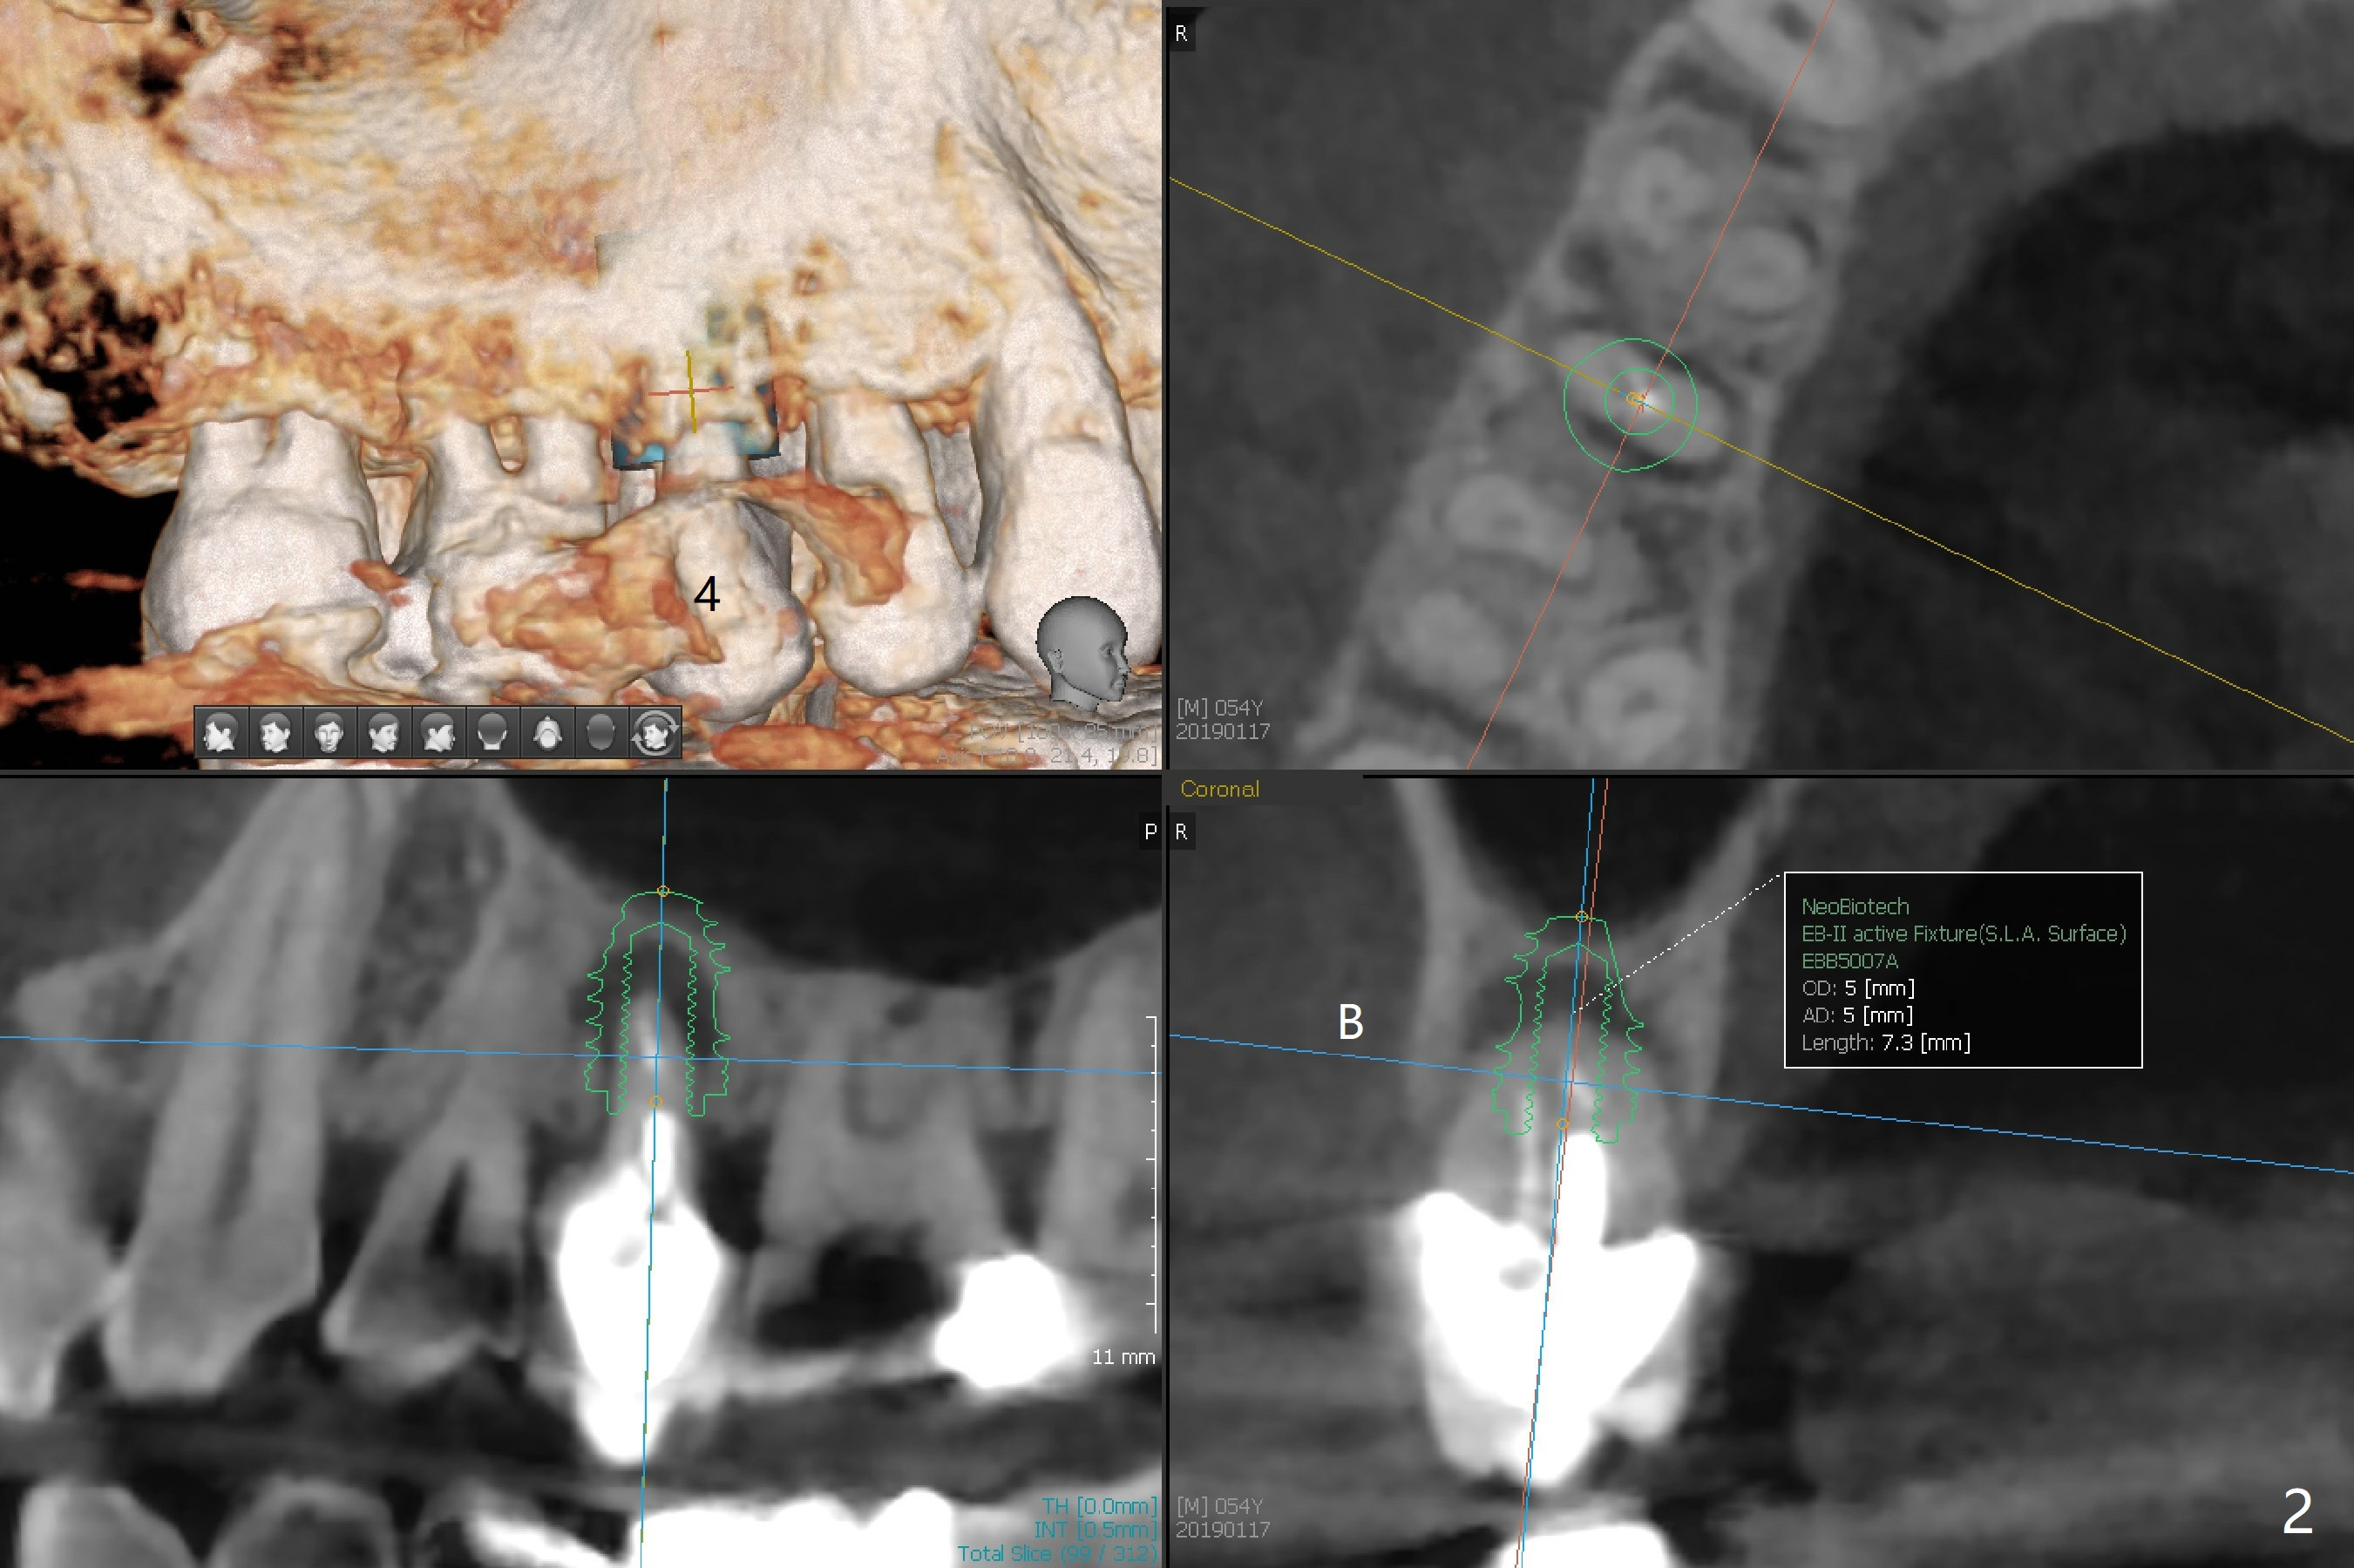

A 54-year-old man with bruxism requests treatment at #4 and 12 with buccal fistulae (Fig.1-3). Due to large defects, a large, but short implants (5x7.3 mm) will be used for primary stability. PRF membranes (x4) and liquid (x1 for sticky bone) will be prepared for sinus lift and buccal defect repair. Guided surgery will be utilized to prevent poor trajectory at #18 and 19 (Fig.1). The result turns out to be good (Fig.4).